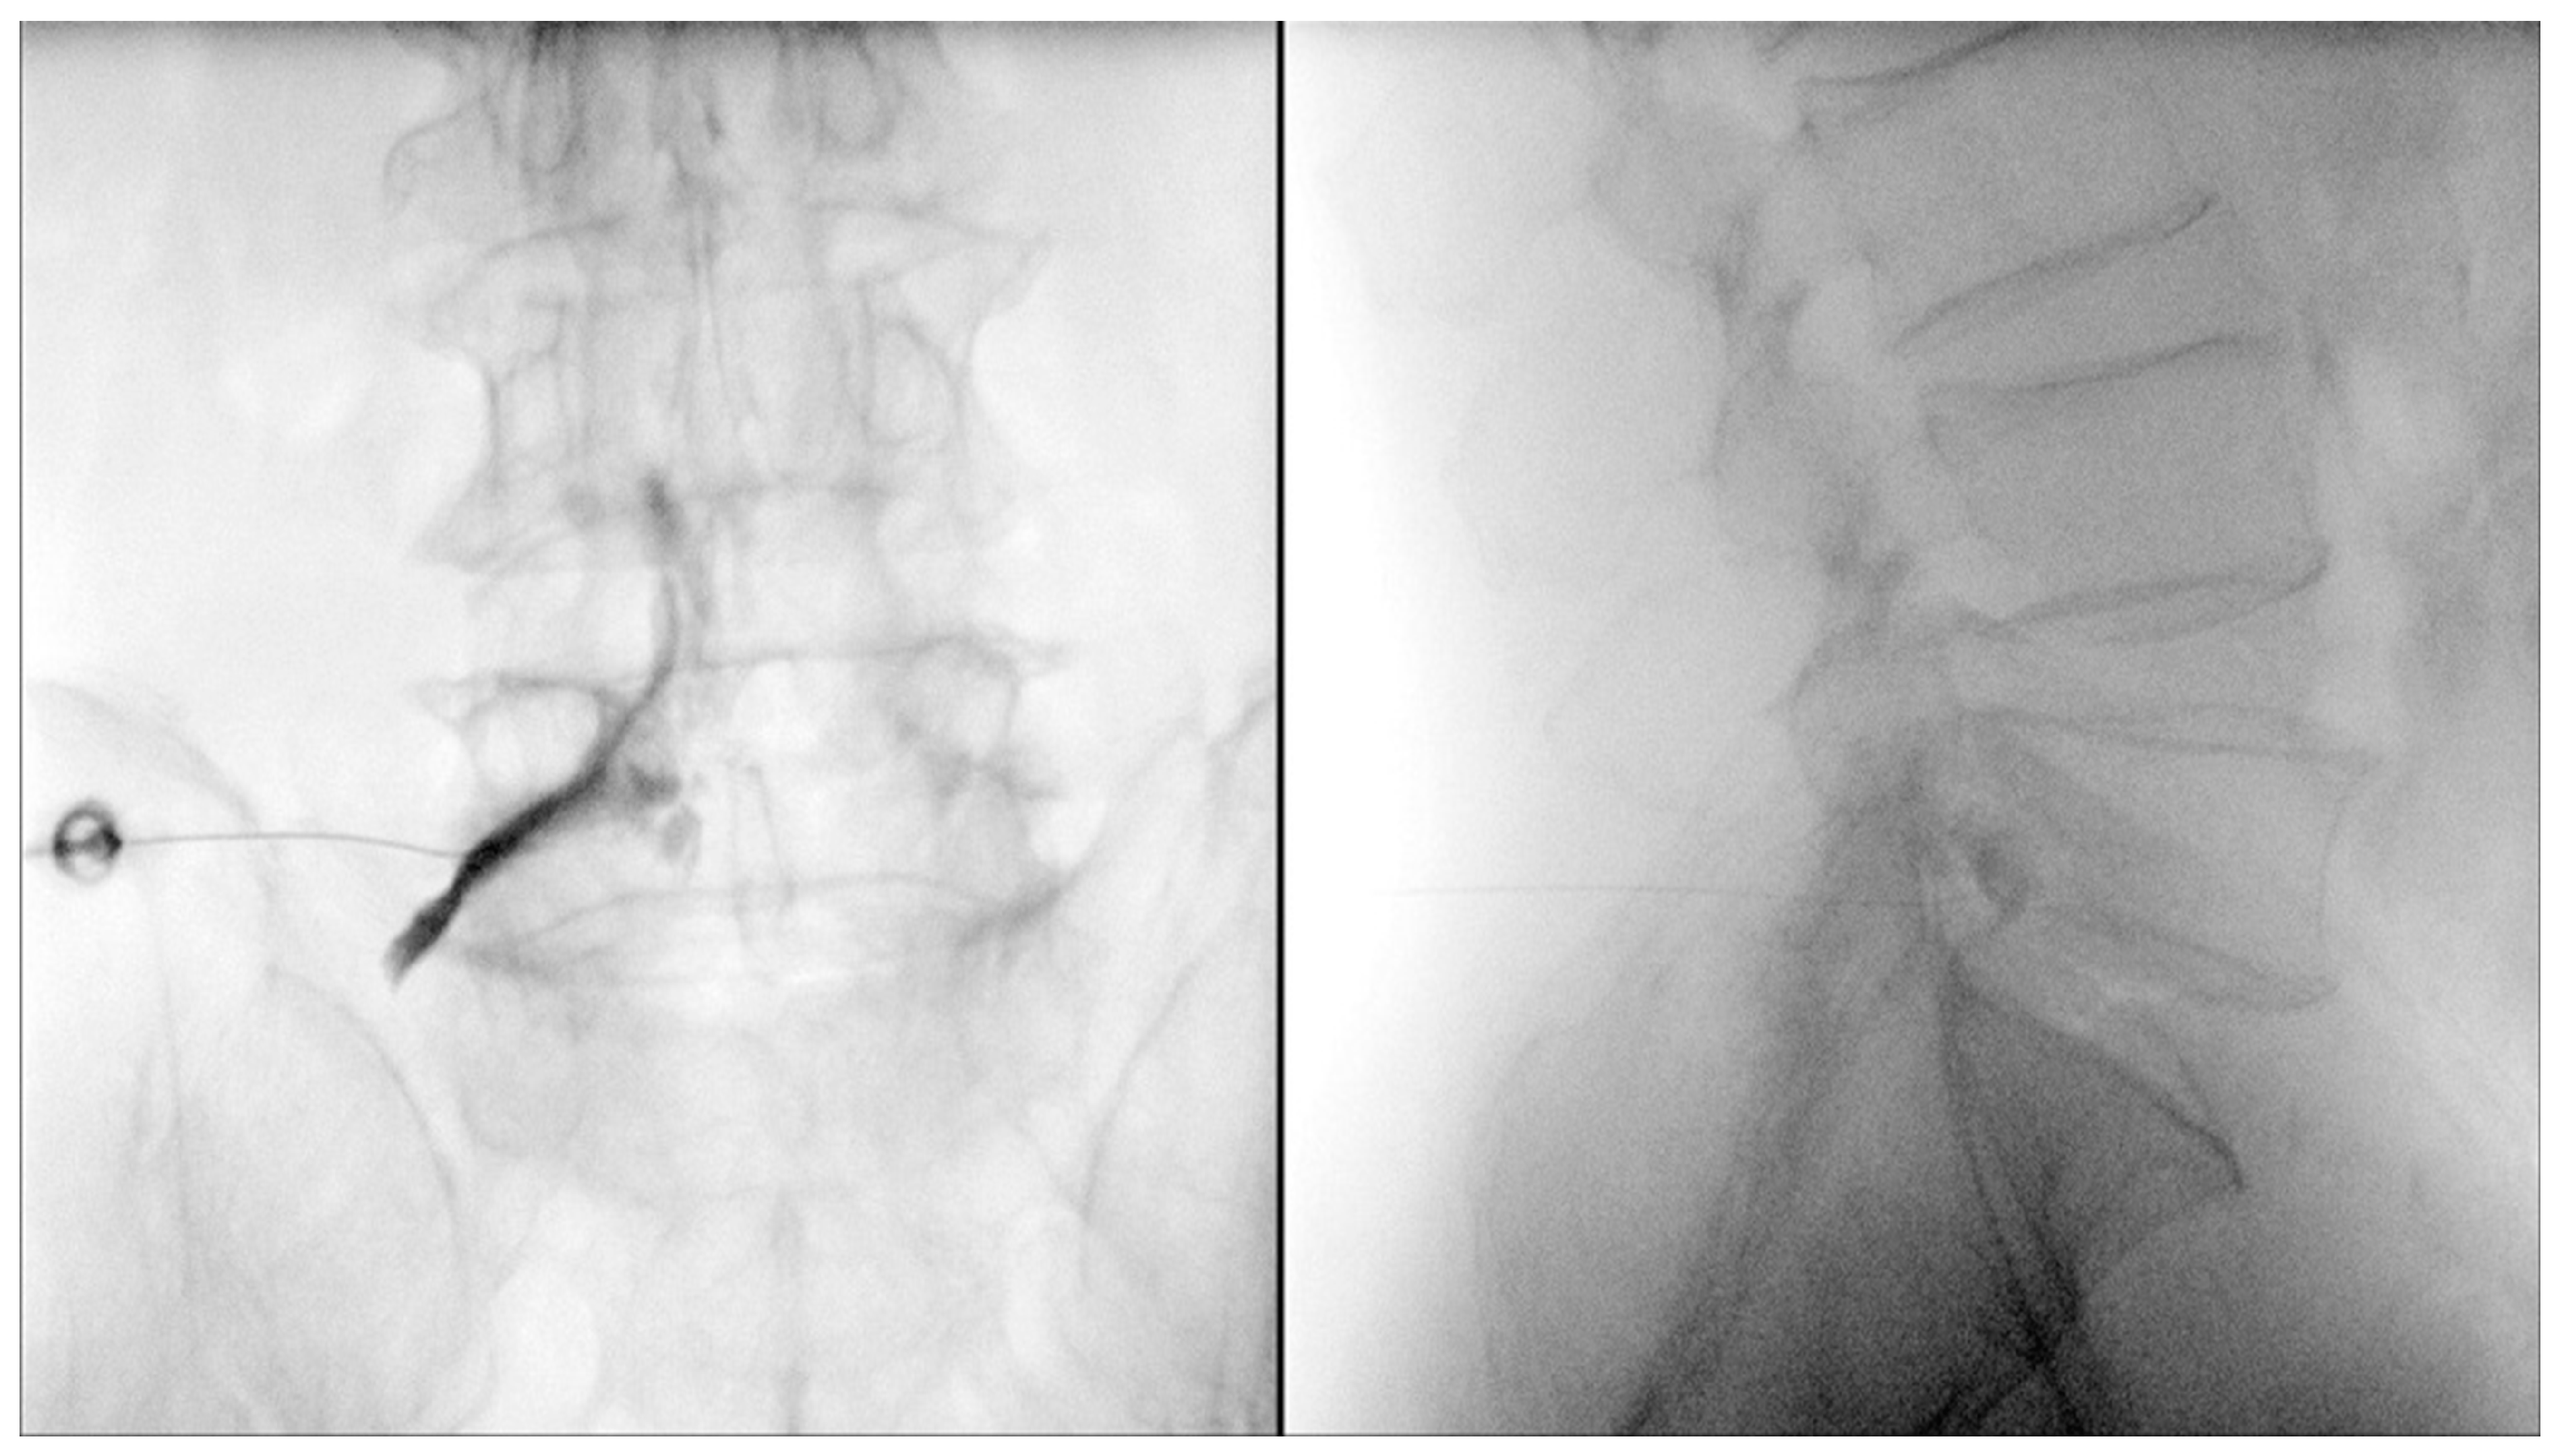

- Park, S.H.; Ji, G.Y.; Cho, P.G.; Shin, D.A.; Yoon, Y.S.; Kim, K.N.; Oh, C.H. Clinical Significance of Epidurography Contrast Patterns after Adhesiolysis during Lumbar Percutaneous Epidural Neuroplasty. Pain. Res. Manag. 2018, 2018, 6268045. [Google Scholar] [CrossRef] [PubMed]